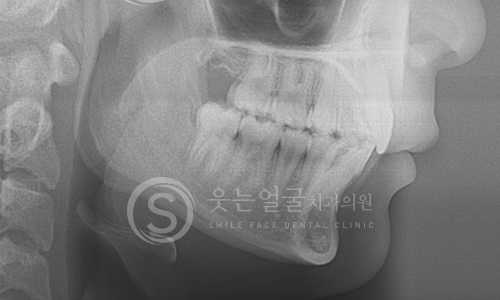

한눈에 보는

임플란트 전후사진